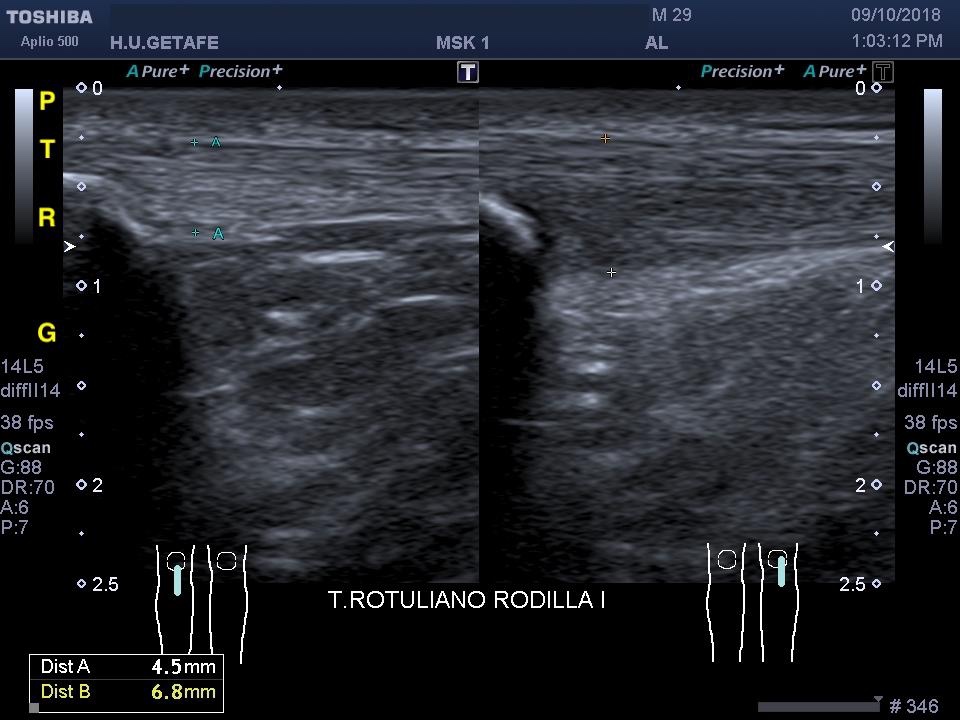

Otra cuestión que nos hace sospechar tendinopatía es el aumento de tamaño del tendón. Esto lo podemos valorar mediante una exploración comparativa con el lado sano.